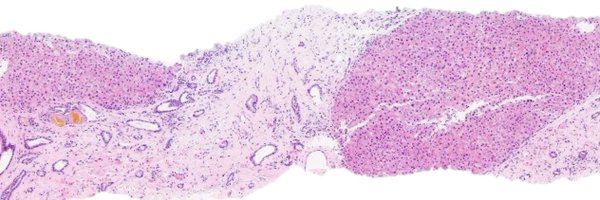

CSPEI 25-6: 63-year-old female with postmenopausal bleeding and total hysterectomy with bilateral salpingo-oophorectomy. ❓ Question: What is the origin of the tubulo-glandular abnormalities? ✍️ Author: Maryam Sharifian, MD Please follow, like, comment, & repost! 🙌